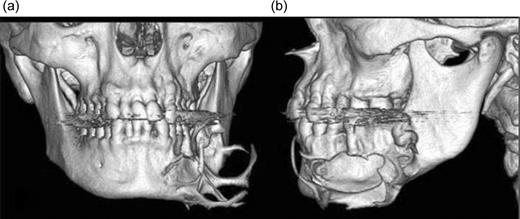

Three-dimensional images allowed for the visualization of the lesion in relation to relevant anatomical structures providing depiction of bone destruction in the body of the mandible. Preoperative 3D CT reconstruction indicated destruction of the buccal cortex of the mandible (left side) caused by the lesion and projection of osseous spiculae (Fig. 1A and B).

Frontal view of pre-operatory 3D CT images shows the destruction of bone and a spiculars osseous formation (a) and in lateral view show the destruction of the cortex (b).